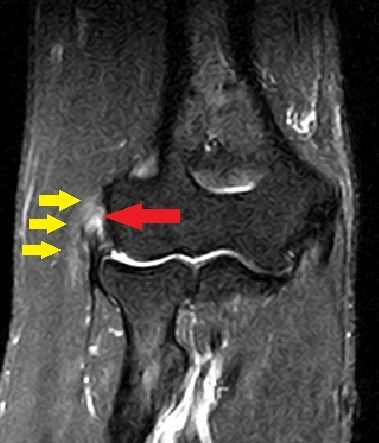

MRI画像

上腕骨外上顆周囲に炎症所見(

黄色  )と、腱付着部に水腫(

赤  )を認め一部線維の剥離を疑います。